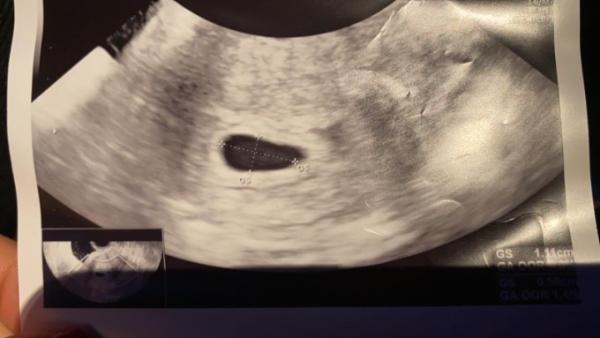

Hallo, War heute bei meiner Ärztin und sie meinte dass die Fruchthöhle leer ist positiv hat sie nicht gesprochen darum mache ich mir jetzt Gedanken kann mir da einer weiterhelfen und meine Gedanken beruhigen danke Im voraus .

Bild zu Fruchthöhle leer in SSW 6+1-2 - Schwanger - wer noch? Rund um die Schwangerschaft

Bei mir war an 6+2 auch nur die Fruchthöhle zu sehen. Bei 8+0 dann auch ein kleiner Embryo mit Herzschlag. Meine FÄ meinte, dass wäre normal. Ich wurde zurückdatiert, aber habe noch keinen neuen Geburtstermin, da sich der Embryo nicht nicht richtig hat ausmessen lassen (saß ganz in der Ecke) . Mach dir noch nicht so viele Gedanken. Viel Glück

Ich war bei 6+4 beim FA und sie konnte auch nur eine Fruchthöhle sehen. Sonst nichts. Bei 7+4 war dann schon alles zu sehen inkl. Herzschlag die Größe des Babys hat zum Anfang immer gestimmt, jetzt wurde ich 5 Tage zurückdatiert. Wann hast du denn deinen nächsten Termin? Da sieht man bestimmt mehr und es ist alles gut

Hallo, mir ging es vor kurzem genauso wie dir! Hatte auch an 6+1 nur eine leere Fruchthöhle im Ultraschall. Habe diesbzgl. auch eine Frage im Expertenforum gestellt. Es hieß in der Antwort abwarten! Das warten hat sich gelohnt. Eine Woche später sah man einen Embryo samt Herzschlag. Wurde auf 6+4 rückdatiert... Eine Woche später war ich dann laut US wieder weiter und schon Anfang der 9 SSW. Nun bin ich in der 10 SSW angekommen und alles sieht gut aus. Du siehst, es kann alles gut ausgehen. Ich würde die Hoffnung nicht zu früh aufgeben. Der Eisprung kann sich immer mal verschieben. Ich hatte anfangs auch kaum Symptome. Die Übelkeit fing bei mir erst kürzlich in der 9 SSW an. Ich wünsche dir und deinem Krümel alles Gute und das die Zeit bis Montag schnell umgeht! LG Visa